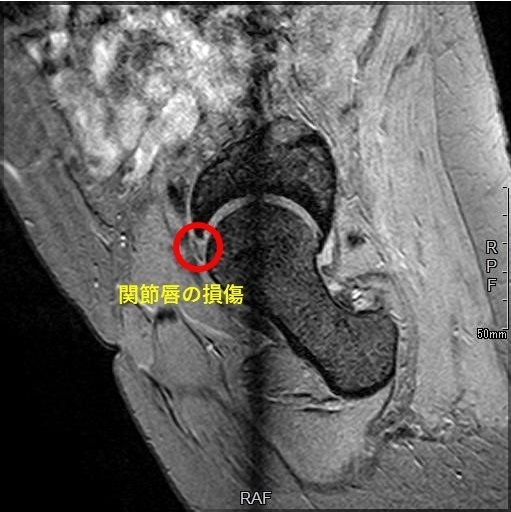

3. MRI検査

通常のレントゲンでは写らない「股関節唇」の断裂や剥離を確認するための最も重要な検査です。高精細なMRIを用いることで、損傷の範囲や程度を詳細に把握します。